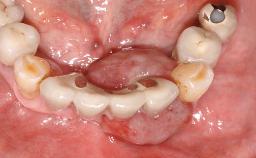

Surgical treatment of a 67-year-old male patient exhibiting an extended edentulous space in the anterior maxilla after the removal of three hopeless incisor teeth.

The video demonstrates implant placement using a surgical stent according to the principle of prosthodontically driven implant placement. The deficient ridge is augmented with locally harvested autologous bone chips, a superficial layer of xenogenic DBBM particles and a resorbable collagen membrane. The surgery is completed with a precise, tension-free primary wound closure.